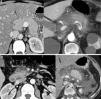

La pancreatitis aguda es una patología común y potencialmente grave que tiene un curso clínico muy variable. Este artículo pretende revisar el papel de las distintas técnicas de imagen en el manejo de esta entidad, describir sus principales manifestaciones radiológicas y la nomenclatura específica asociada a esta entidad.

Acute pancreatitis is common; the clinical course of this potentially severe condition varies widely. This paper aims to review the role of different imaging techniques in the management of acute pancreatitis, describe the main imaging findings for this entity, and explain the terms and criteria used to classify them.